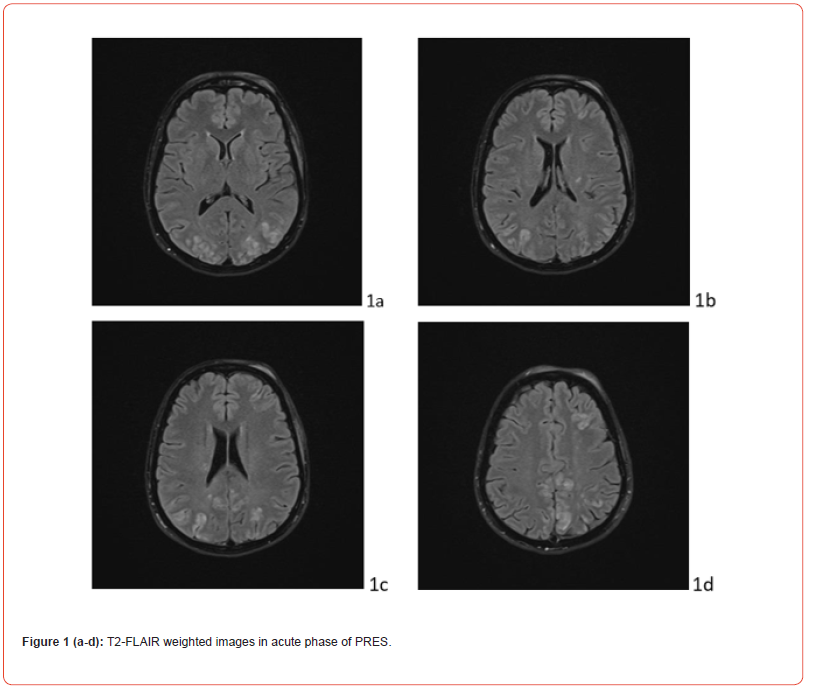

The gold standard in diagnosis is represented by Nuclear Magnetic Resonance (MRI), particularly the sequences obtained in relaxation time 2 (T2) and Fluid Attenuated Inversion Recovery (FLAIR). The most characteristic imaging pattern is the presence of oedema in the white matter of the posterior regions of both cerebral hemispheres, typically in the parieto-occipital regions. Timely diagnosis and multidisciplinary decision-making regarding the most appropriate therapy are essential to avoid complications and short- and long-term outcomes. We report the case of PRES during puerperium in a young woman, with no risk factors and predisposing conditions.

In the post-critical phase, the patient appeared in a mild state of confusion with amnesia of the event. Vital signs continuously monitored from the first episode were normal, except for a BP measurement of 155/90 mmHg. The patient underwent neuroimaging. Cranial computerized tomography showed a swelling of the genienal soft tissues on the left, with tenuously hyperdense tissue, related to mild extravasation of blood, because of the trauma. T2 FLAIR MRI showed alterations in the cortico-subcortical signal, not only in bilateral parieto-occipital regions, but also in frontal lobes and at the vertex (Fig.1 A). Clinical picture, supported by MRI findings, confirmed the diagnosis of PRES. Anti-inflammatory, analgesic, anti- epileptic, anti-hypertensive and anti-oedema therapy was set up according to the following scheme: Perfalgan 1000 mg 1 vial, bid, iv; Decadron 4 mg 1 vial x 3, iv; Levetiracetam 500 mg/5 ml 2 vials in 500 ml 0,9% sodium chloride solution in 24 hours, Nimodipine 5 drops x 3, after BP control; osmotic therapy was suggested in case of symptoms and signs of intracranial hypertension. During post-critical observation, vital signs were normal, except for a BP value of 152/94 mmHg. The hydroelectrolyte balance and blood chemistry tests were normal. The condition of the patient improved rapidly. At day 9, the patient was discharged wit maintenance therapy and an indication of follow-up at one month. The last EEG and MRI check, performed at month IV, showed a complete regression of the clinical picture (Figure. 1 B).

MRI of the brain is the gold standard diagnostic tool. It allows early detection of diffuse vasogenic oedema of the white matter, its posterior site, in the parieto-occipital regions, extent of damage, differential diagnosis with other pathological conditions. The peculiar lesions of PRES are symmetrical, hypointense in T1-weighted sequences, hyperintense in T2-weighted and T2 FLAIR sequences, isointense or mildly hyperintense in DWI. They have a watershed pattern [29]. Apparent diffusion coefficient (ADC) maps may show normal or increased diffusion in the case of vasogenic edema (signal hyperintensity), restricted in the case of cytotoxic edema (signal hypointensity). Following gadolinium administration, linear or perimetral enhancement (gyrus-like) was observed in 20% of patients. PRES is considered mild when cortical and subcortical white matter oedema is present, without mass effect, herniations, hemorrhages, minimal involvement of another region (cerebellum, brainstem, basal nuclei). Moderate PRES is defined by the presence of confluent oedema extending from the cortex to the deep white matter without extension to the periventricular regions or mild involvement of two of the other regions indicated above (cerebellum, brainstem and basal nuclei). A mild mass effect may be present, without herniations or midline shifts, hemorrhages. Severe PRES is characterized by confluent oedema extending from the cortex to the ventricles, midline shift or herniation due to oedema or hemorrhage, involvement of three other regions (cerebellum, brainstem, and basal ganglia) [30]. As mentioned above, DWI sequences and ADC maps are useful for distinguishing vasogenic edema from cytotoxic edema, typical of hypoperfusion in cases of cerebral infarction or other conditions, such as inflammatory, demyelinating and space-occupying lesions. However, small areas of restriction of diffusion and large areas of vasogenic oedema are found in 15-33% of PRES patients [31,32]. These, hyperintense in DWI, hypointense in ADC maps, indicate cytotoxic edema and are predictive of incomplete recovery and poor prognosis [33]. The study of intracranial vessels with MRI with angio sequences, CT angiography and transcranial Doppler ultrasound are indicated for the differential diagnosis with reversible cerebral vasoconstriction syndrome, which also appears with intense headache in the postpartum period [34]. Cerebral hemorrhages are found in 10–30% of cases.